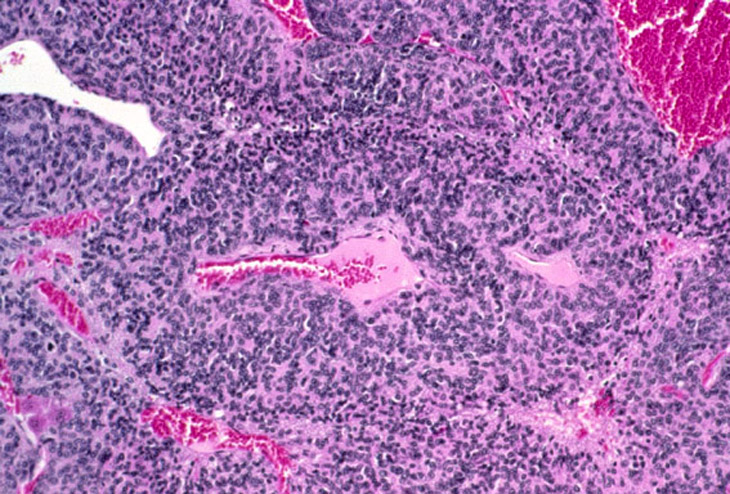

A large hepatoblastoma; higher magnification shows malignant cells palisading around vascular structures.